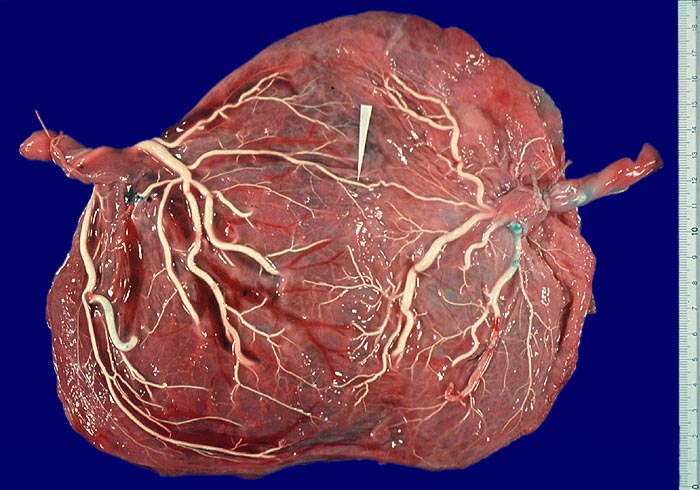

Zwillingsplazenta mit arterio-arterieller Anastomose

Die Arterien erscheinen nach Injektion weiss. Der Pfeil zeigt auf eine Arterie, die über die Grenze der Versorgungsgebiete der beiden Plazenten hinweg mit einer Arterie der Gegenseite anastomosiert.

Arterien verlaufen in der Plazenta über den Venen und können deshalb aufgrund ihres Verlaufs auch ohne vorherige Injektion von den Venen unterschieden werden.